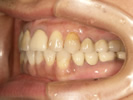

50代女性

![]() |

治療前 |

||

治療中。仮歯。 左上の奥にインプラント埋入。 噛みあわせ治療を行いました |

治療後 全体の歯で食事がおいしくできるようになったと喜んでおられました。 |